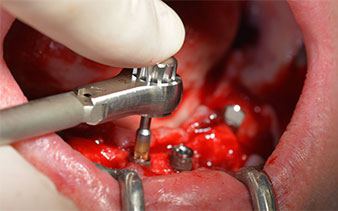

After removal of the residual dentition in the mandible, the alveolar crest was exposed from 37 to 47.

The mental foramen was first identified as a limiting anatomical structure and then the cortical bone of the crest was smoothed with the straight handpiece and a large rose-head bur (Fig. 4).

High primary stability is an absolute requirement for an immediate restoration. In order to achieve this, the hole was not tapped in this case. The W&H Implantmed drill unit used here is equipped with a suitable special mode for this, which can also be directly selected and is indispensable for many indications. The final revolutions when placing the implants exceeded the value of 32 Ncm and were performed by hand. In such cases, we recommend utilizing the implants’ self-tapping function and twisting the implants backwards and forwards several times. This allows the implant to approach the final position gradually without exerting excessive pressure on the bone (Fig. 14).

Angled abutments (35°) were screwed in to compensate for the divergence of the distal implants, with the result that the emergence profile of all implants was as perpendicular as possible to the bite plane. This is a prerequisite for occlusal placement of the provisional and subsequently the permanent denture (Fig. 15 and 16).